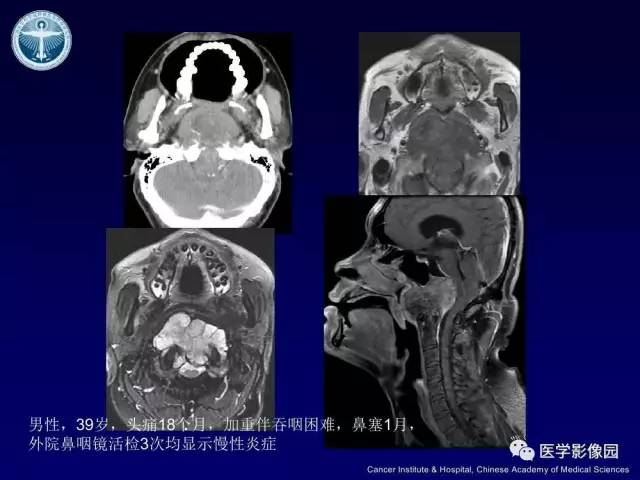

【病例】左侧颈静脉孔区脊索瘤1例MR影像表现